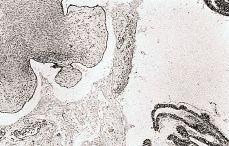

Macroscópicamente, al corte la masa era quística unilocular con contenido de líquido seroso claro. La cara interna era lisa, salvo varias zonas de proyecciones papilares de 0,6 a 1 cm de diámetro. A la observación microscópica se observaron numerosas papilas de diversos tamaños que mostraban un estroma de tejido fibroso que variaba desde altamente celular, intensamente hialinizado hasta severamente edematoso, con numerosas zonas de transición entre estas posibilidades coexistiendo en la misma papila (Fig. 2). Las papilas estaban superficialmente tapizadas por monocapa de células epiteliales predominantemente cuboidales o columnares, pudiendo verse con mucha menor frecuencia células ciliadas, células «en tachuela» e incluso células claras. El borde luminal de las células mostraba positividad para el Azul Alcian y el PAS con predigestión con diastasa. No observamos ni multiestratificación, formación de penachos, atipias celulares, mitosis ni «cuerpos de psammoma». Con todas estas características histológicas efectuamos el diagnóstico de cistoadenofibroma seroso papilar desarrollado en un quiste paramesonéfrico paratubárico.

Figura 2.Detalle del tumor. Mezcla de papilas edematosas con otras con estroma fibroso, así como papilas transcionales (H & E, x100).